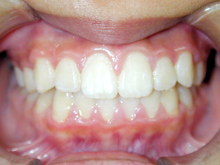

南粕谷在住 M.H様(32歳女性)

M.H様は矯正相談にて来院され下の前歯がガタガタであることを主訴に来院されました。

下顎前歯の叢生の改善のために部分矯正を希望されました。下顎の前歯群には中等度の叢生がみられます。

神経系の慢性疾患のためお薬の副作用の影響で歯肉の腫脹が目立っています。

むし歯の有無や歯周病の程度、修復物の状態などの口腔内検査を行い、

レントゲン写真、口腔内写真、正貌と側貌の写真撮影を行い診断のための資料を採取しました。

![]() |

下顎前歯の叢生の改善するためには上下顎前歯の接触が緊密なために上顎の前歯の矯正治療が必要となります。

臼歯関係、犬歯関係ともに1対2歯でよく咬んでいますので

咬み合わせの関係を壊すことなく上下顎の前歯の叢生を部分矯正で改善をめざします。

側貌から口元には緊張がなく突出を認めなかったので非抜歯で矯正治療できると患者様にはお伝えしました。

薬物の副作用の影響の歯肉の腫れは叢生の改善によりブラッシングが容易になると改善されることを期待します。

上下顎の前歯を前方へ移動させ、その状態により前歯のストリッピングを行うなどを計画します。

上顎の前歯部分の矯正治療を先行させます。上下顎前歯の接触状態をみてその後、下顎の小臼歯部までブレースを接着します。

部分矯正ですがブレースを接着する部位は咬み合わせの安定のために広範囲となります。

上顎のワイヤーをステップアップし、下顎にブレースが付くようになった時点で下顎に最初のワイヤーを装着します。

ストリッピングを行うことなく上下顎の前歯の叢生は改善されました。

上顎両側側切歯の歯肉の腫れは消退し、下顎前歯の叢生の改善により歯肉の腫れは消退傾向がみられます。

今後は上顎中切歯の歯間乳頭の腫れを軽減するためブラッシング指導と保定治療時のPMTCを継続する予定です。

矯正歯科治療で歯列が改善されたことで歯口清掃が容易になり、常用薬剤の副作用である歯肉腫脹は軽減されています。

治療費用:50万円

動的治療期間:1年6か月